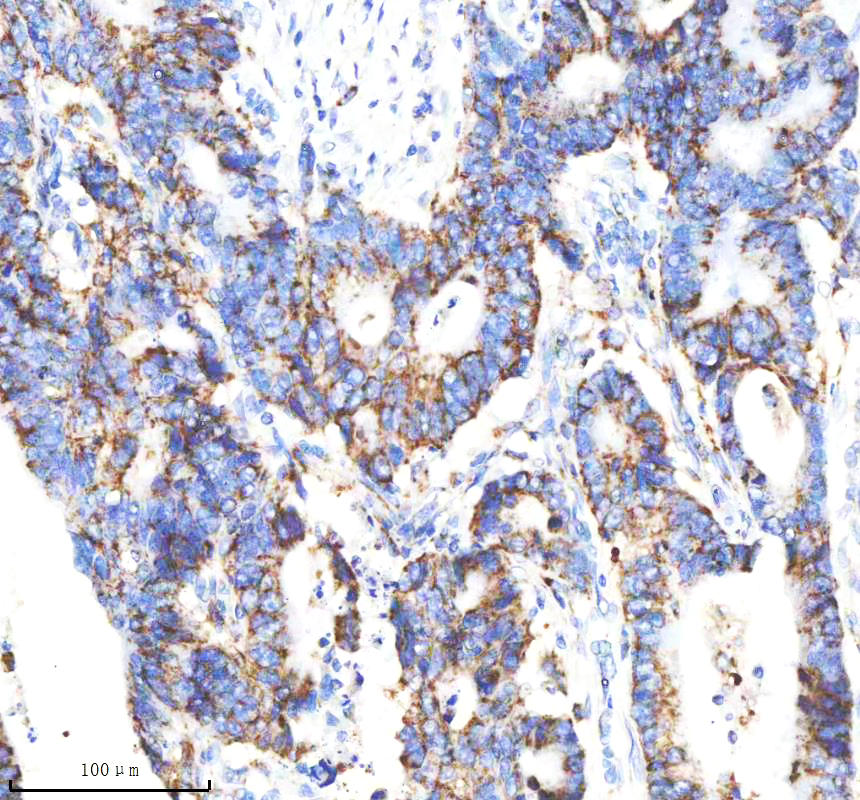

IHC analysis of VDAC1 using anti-VDAC1 antibody (BM4279) .

VDAC1 was detected in a paraffin-embedded section of human stomach cancer tissue. The tissue section was incubated with rabbit anti-VDAC1 Antibody (BM4279) at a dilution of 1:200 and developed using HRP Conjugated Rabbit IgG Super Vision Assay Kit (Catalog # SV0002) with DAB (Catalog # AR1027) as the chromogen.